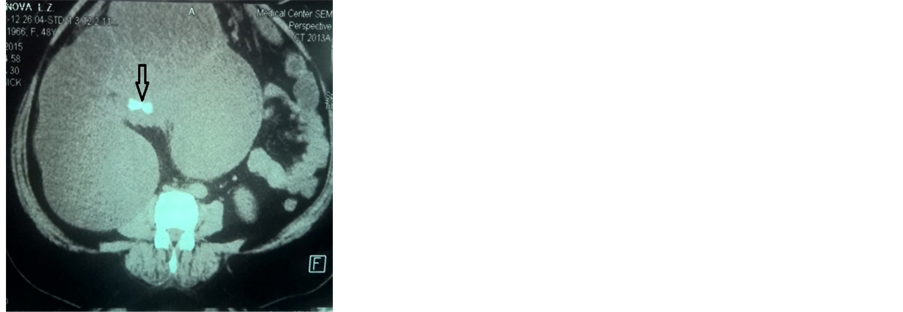

Macroscopically, the material of the nephrectomy had parts of white and brown in color; it was 32 × 18 × 7 cm in size and 1210 g in weight, with cystic nodularity as shown in Figure 2. The anatomo-pathology’s result was hydronephrosis and chronic pyelonephritis. The germ found was Escherichia coli. E. coli was identified as medium, pink-to-red colonies and was confirmed by positive indole test.

Figure 2. Macroscopic view of the kidney.